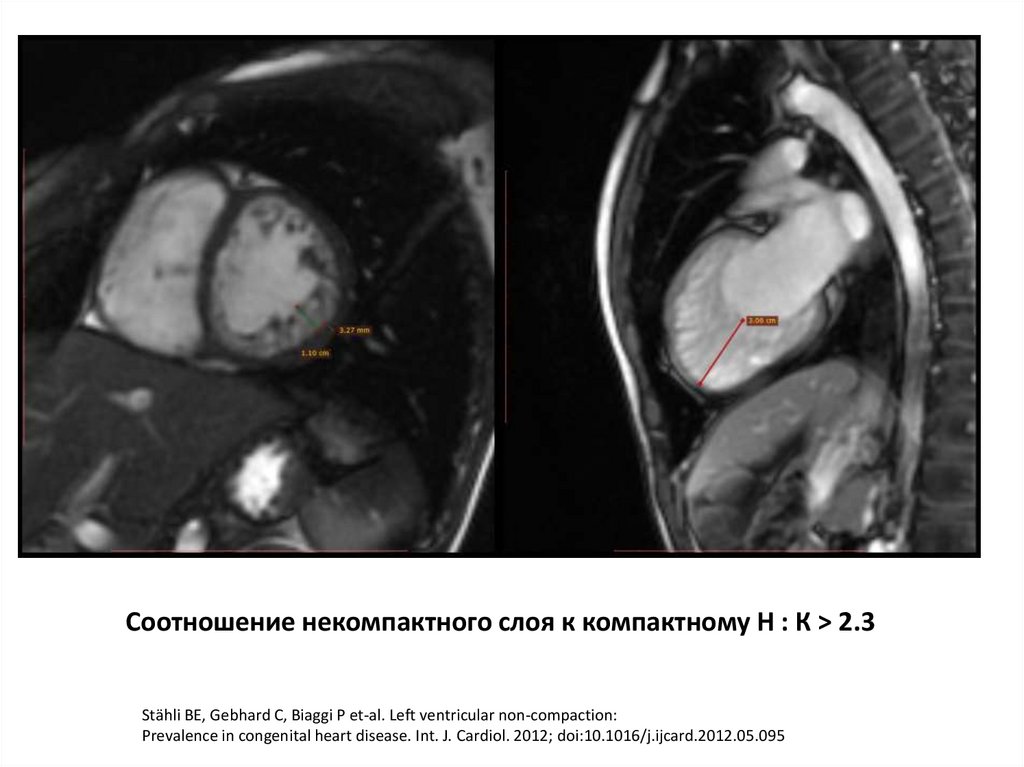

Некомпактный миокард

Соотношение некомпактного слоя к компактному Н : К > 2.3

Stähli BE, Gebhard C, Biaggi P et-al. Left ventricular non-compaction:

Prevalence in congenital heart disease. Int. J. Cardiol. 2012; doi:10.1016/j.ijcard.2012.05.095